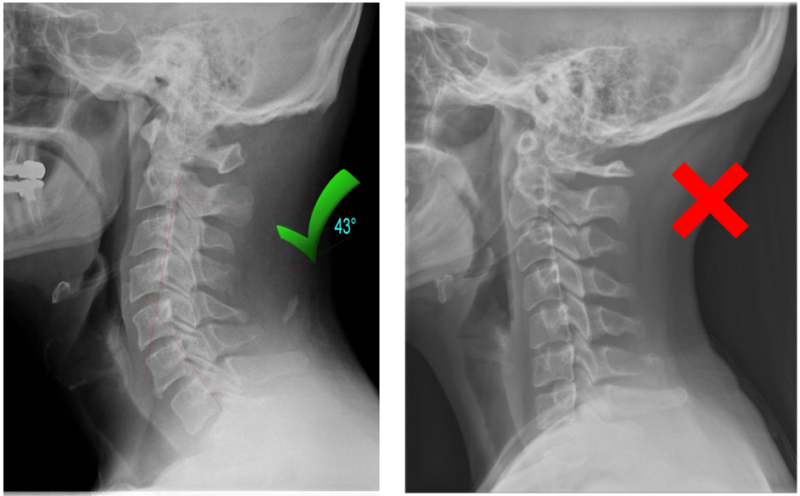

Did you know that each region of your spine should have a specific curve for maximum health and function? Your neck or cervical spine in particular should have a backward (or lordotic) curve to it. It’s similar to the curve we should have in our lower back. It’s something we all develop as babies when we learn to keep our heads up. That’s why “tummy time” is so important for infants! It develops these two lordotic curves which are necessary to allow for maximum spinal cord diameter (and trust me, that is something that we all want and need).

This normal curved position of your neck is where all of your associated muscles and most importantly, your spinal cord are at the healthiest levels of tension. You are FAR, FAR less likely to have pain at the base of your skull, cervicogenic headaches, or neck problems when you maintain this position of your neck. When we have bad posture it puts this neck curve in the opposite direction which can lead to several things which I won’t cover in detail but will mention a few.